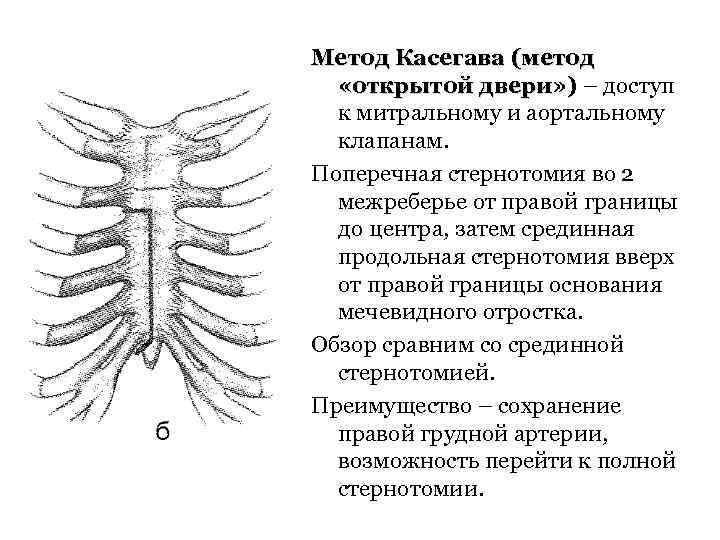

Метод Касегава (метод «открытой двери» ) – доступ к митральному и аортальному клапанам. Поперечная стернотомия во 2 межреберье от правой границы до центра, затем срединная продольная стернотомия вверх от правой границы основания мечевидного отростка. Обзор сравним со срединной стернотомией. Преимущество – сохранение правой грудной артерии, возможность перейти к полной стернотомии.

Метод Касегава (метод «открытой двери» ) – доступ к митральному и аортальному клапанам. Поперечная стернотомия во 2 межреберье от правой границы до центра, затем срединная продольная стернотомия вверх от правой границы основания мечевидного отростка. Обзор сравним со срединной стернотомией. Преимущество – сохранение правой грудной артерии, возможность перейти к полной стернотомии.